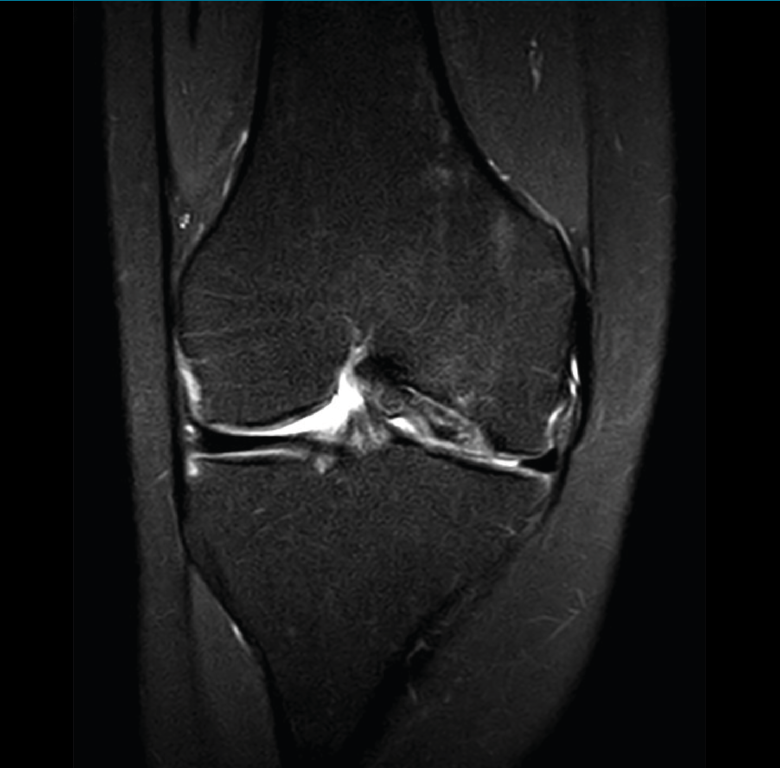

Figura 35. Corte de secuencia coronal y sagital de resonancia magnética de rodilla: rotura en asa de cubo del menisco interno con fragmento desplazado al intercóndilo.

1.2. Ligamentos

Se visualizan como estructuras lineales hipointensas en todas las secuencias.